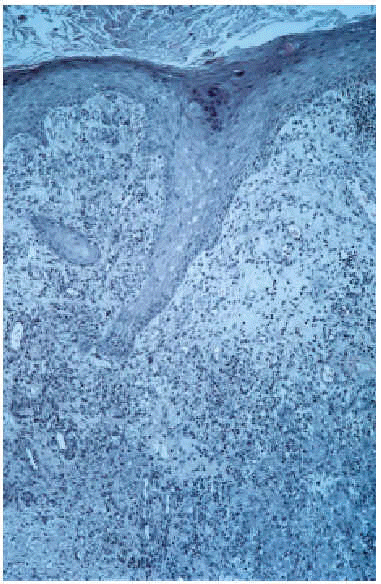

El estudio histológico de la lesión, con hematoxilina-eosina, mostró una hiperplasia epidérmica pseudoepiteliomatosa y en toda la dermis una intensa reacción inflamatoria de tipo granulomatoso, constituida por células epitelioides, células gigantes multinucleadas, plasmáticas y neutrófilos, formando en algunos puntos microabscesos (fig. 2). Asimismo se evidenciaba la presencia de abundantes formaciones esporuladas, de pequeño tamaño (entre 5 y 15 µm), pigmentadas, con gruesa pared y en algunas de ellas tabicación central, localizadas tanto en dermis como en microabscesos que se eliminaban hacia la superficie epidérmica (fig. 3). Dichas formaciones presentaron positividad en la tinción con PAS (fig. 4). En el cultivo de biopsia en agar de Sabouraud se aisló la especie Wangiella dermatitidis, lo que permitió establecer el diagnóstico de cromoblastomicosis.

Fig. 2.--Hiperplasia epidérmica pseudoepiteliomatosa con intensa reacción inflamatoria de tipo granulomatoso en toda la dermis, constituida por células epitelioides, gigantes multinucleadas, plasmáticas y neutrófilos (hematoxilina-eosina, x40).